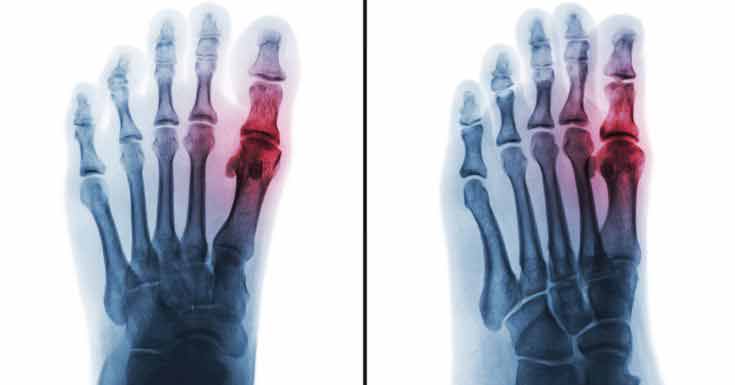

Metabolic Arthritis

When uric acid accumulates in excess at the level of a joint, inflammation and pain will occur as symptoms.

This condition is known as metabolic arthritis or gout; the crystals of uric acid are also presented as purines and they often affect the joints of the big toe, preventing the patient from walking or bearing weight on the respective foot.

This can lead to what is known as a gout attack, which is characterized by severe inflammation and intense leg pain. The affected joints are warm to the touch and a pulsating sensation can be present.